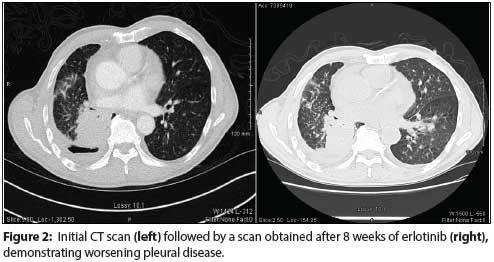

The Case: An 81-year-old Chinese male never-smoker with a medical history of hypertension and hyperlipidemia presented with a productive cough and a 5-lb weight loss over 3 months. A chest x-ray revealed a mass in the right lower lobe of the lung, which was confirmed by CT of the chest. A positron emission tomography (PET)/CT scan showed a right lower lobe mass with a standardized uptake value of 9.1 and revealed additional bilateral lung nodules and bulky, bilateral mediastinal lymphadenopathy. A transbronchial biopsy revealed poorly differentiated adenocarcinoma, with immunostaining positive for TTF1 and negative for P40. Epidermal growth factor receptor (EGFR) testing by direct Sanger sequencing identified two separate EGFR mutations: an L858R mutation in exon 21 and a de novo T790M mutation in exon 20 (Figure 1). Based on the activating mutation in exon 21, erlotinib, 150 mg PO daily, was initiated. Although the patient tolerated the drug without any adverse events, a PET/CT scan 8 weeks later revealed increased burden of intrapulmonary metastatic disease, a worsening pleural effusion, and new destructive bony lesions in the posterior T5 and L1 vertebral bodies (Figure 2). The patient was offered systemic chemotherapy and instructed to discontinue erlotinib. Despite this recommendation he declined any further therapy and eventually enrolled in an outpatient hospice program. He died approximately 1 year after diagnosis.